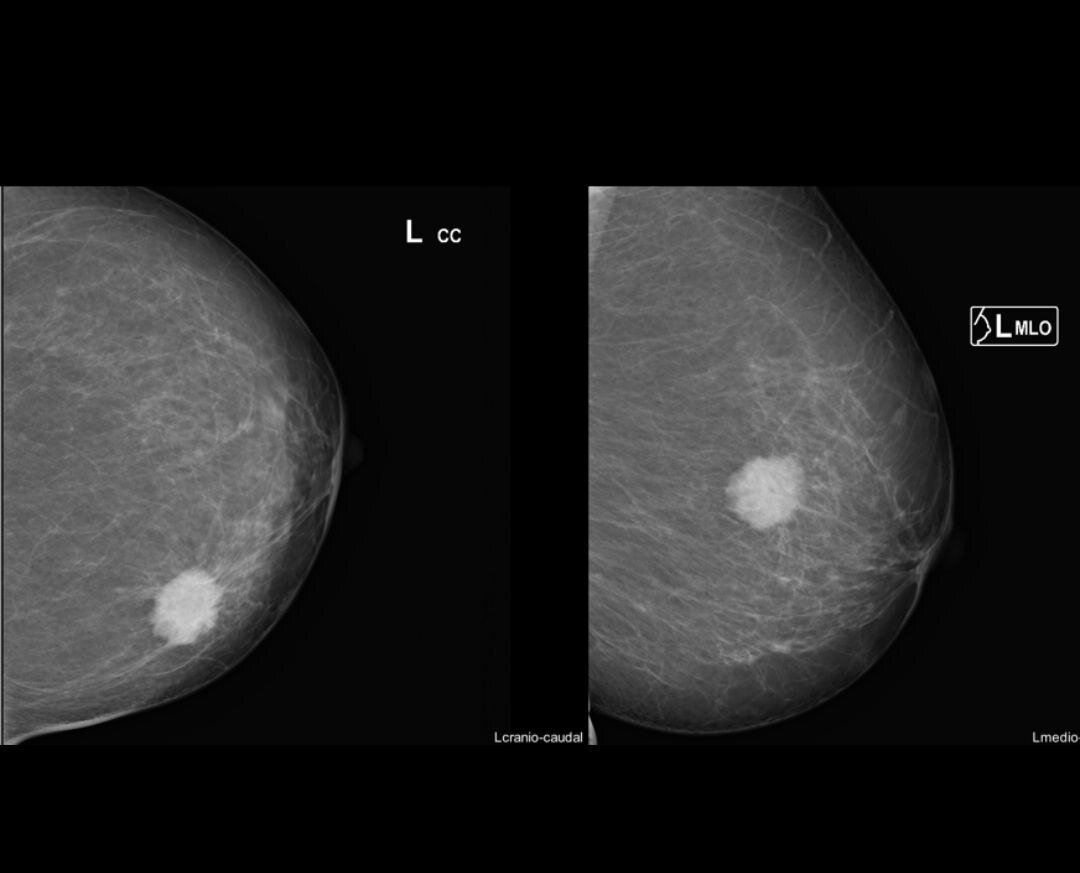

Вариант РМЖ на этапе диагностики

Внутритканевая разметка, установка иглы-гарпун. Выполняется под УЗИ или рентгеном. В данном случае - под УЗИ.

Необходима при непальпируемых опухолях для хирурга. Диагноз РМЖ Т1N0M0, метка устанавливается под местным обезболиванием.

Каждый биологический подтип: Люминальный А, Люминальный В, Her позитивный вариант, триждынегативный имеют свои особенности соно- рентгенологической картины, что позволяет уже на этапе диагностики предположить вариант рака РМЖ.